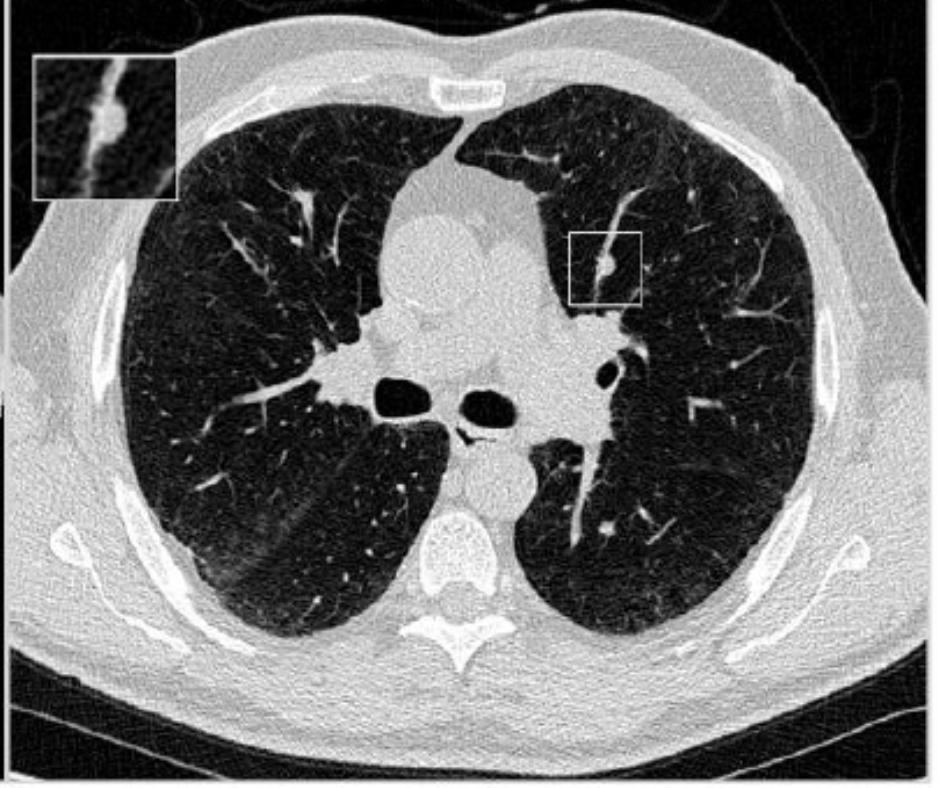

Modifications to pack-year history and smoking quit duration thresholds beyond those recommended in the 2021 United States Preventative Services Task Force (USPSTF) criteria for low-dose computed tomography lung cancer screening may more than double the number of increased lung cancer cases physicians would see with application of the 2021 USPSTF screening criteria.